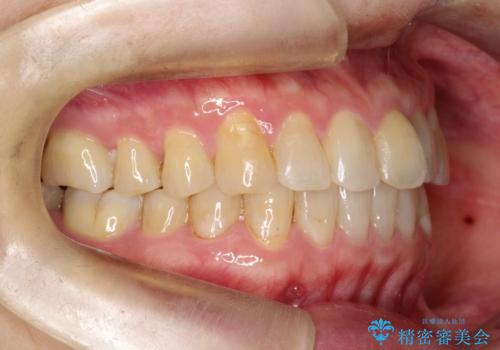

【インビザライン】前歯のガタガタを治したい

- 前歯のガタガタを主訴に来院されました。

上の歯の前突も気になってたため、奥歯の遠心移動も行いながらインビザラインにて治療を行いました。

前歯も下がり満足していただきました。

今回は奥歯の遠心移動とIPRを行って配列しています。